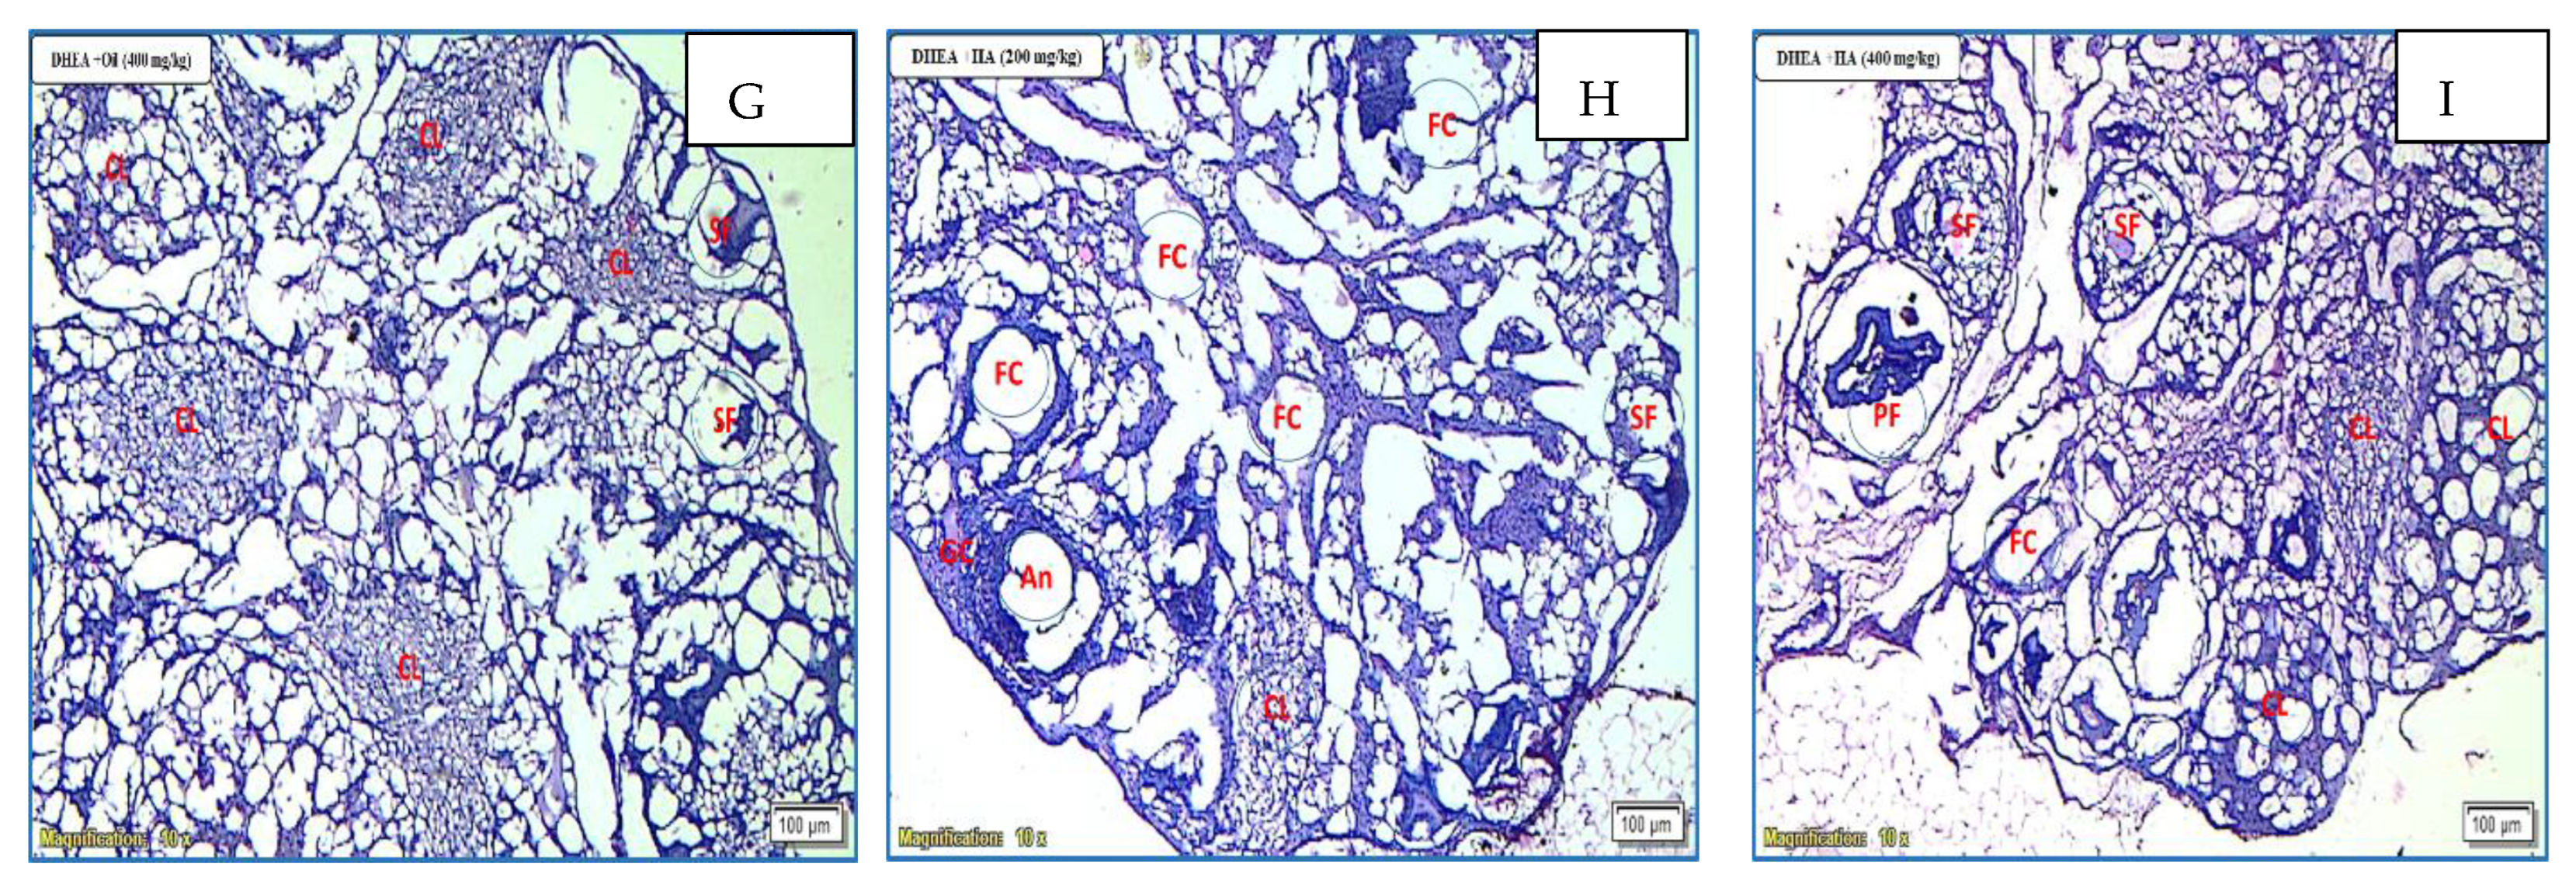

3.11. Histopathological Examination of the Ovaries